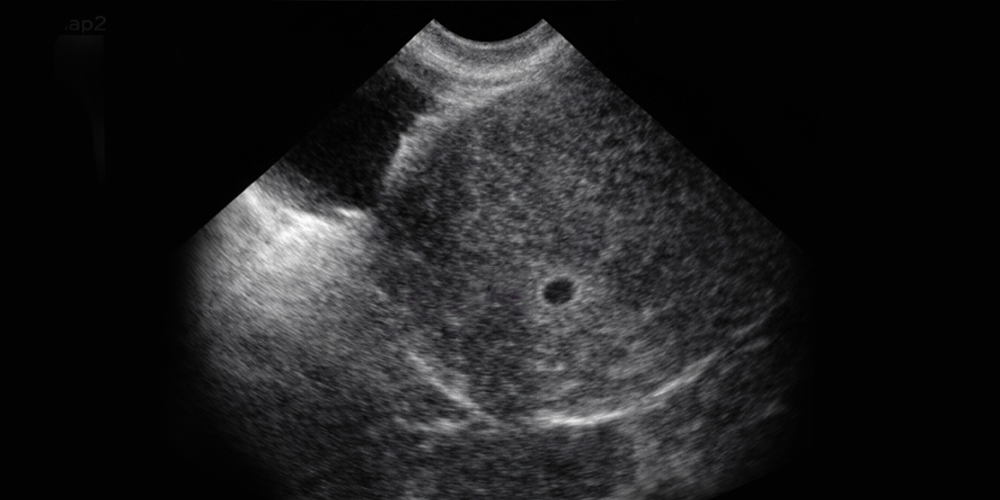

Varsa normal yerinde mi yoksa dış gebelik mi olduğudur. Başlayan gebeliklerin yaklaşık % 1,5'u dış gebelikle sonuçlanır. Az bir oran değil... Kanda gebelik hormonu 1500 ünitenin üzerindeyse gebelik kesesi görülebilecek büyüklükte demektir. Normal yeri, yani rahmin içi boş görülüyorsa, dış gebelik akla getirilmelidir. Gebelik hormonu yani hCG düzeyi 1500'ün altındaysa dış gebelik yine de bir ihtimal olmasına rağmen normal ama sadece henüz çok küçük olduğu için görülemiyordur. Birkaç gün sonra tekrar muayene ile durum aydınlanır. Aşağıdaki şekilde normal gebeliğin en erken hali izlenmektedir.

Seksende bir ihtimalle karşılaşılan ikiz gebelik ( çift yumurta ikizi) bu ilk muayenede belli olabilir.